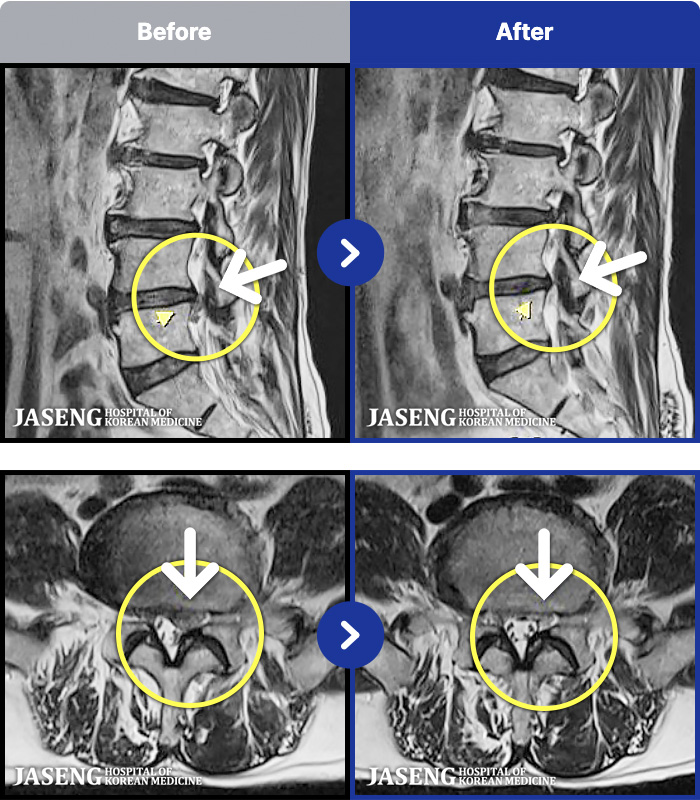

[] 23.11.11~25.06.04